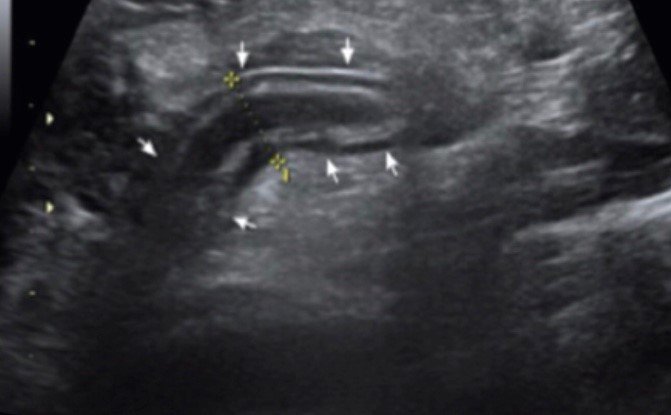

Upala crvuljka, latinskog naziva apendicitis, je relativno česta akutna upala, koja, ako se ne prepozna na vrijeme i ne liječi može imati smrtni ishod. Crvuljak se nalazi u desnom donjem dijelu trbuha, već prema zdjelici i u prosjeku je duljine 7cm, promjera 0,6cm. Kada dođe do upale, u cjelosti se poveća i postaje bolan na pritisak trbuha u njegovoj razini. Najčešći simptom je bol, desno prema zdjelici i oko pupka, pa čak i u žličici. Dolazi i do povraćanja, a često se javlja i povišena temperatura. Kod djece može biti osjetljiv cijeli trbuh, a često slično se ponaša upala limfnih čvorova u trbuhu. Kod žena teško se razluči od upala jajnika, zdjelice, pa čak i ovulacije. Zato je ponekad nužan pregled iskusnog ginekologa. Ako navedene tegobe ne prestaju kroz nekoliko sati, a čak se i pogoršavaju, mora se obratiti liječniku, koji će nakon pregleda i laboratorijskih nalaza posumnjati da se radi o upali crvuljka, a što se sa velikom sigurnošću može potvrditi ultrazvučnim pregledom. Za postavljanje ispravne dijagnoze nužan je kvalitetan ultrazvučni uređaj, te liječnik sa iskustvom u ovom području. Pregleda se ultrazvukom cijeli trbuh, a potom se usredotoči na desni donji dio trbuha i zdjelice, te se aktivno traži duguljasta struktura slijepog završetka promjera većeg od 0,6 cm, koja se ne može stisnuti, tj. pritiskom joj se ne može smanjiti promjer, a dobro je prokrvljena, te odgovara upaljenom crvuljku. Nakon potvrde na upalu bolesnik se upućuje hitno kirurgu. Važno je upalu crvuljka prepoznati na vrijeme jer odgađanjem dolazi do puknuća-perforacije i razlijevanja po trbušnoj šupljini što može dovesti do ozbiljnih upala potrbušnice. (Ultrazvučna slika upaljenog crvuljka)